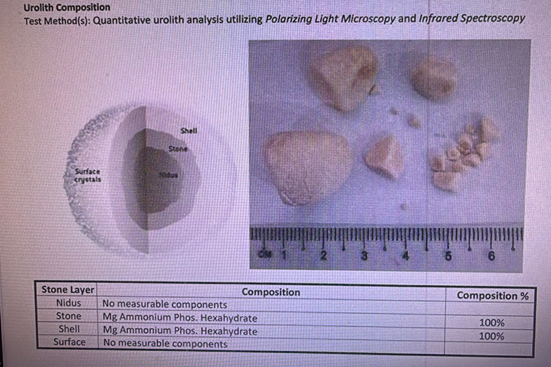

Stone Composition Analysis

Analysis of the stone composition revealed that the bladder stones in this case were primarily composed of Magnesium Ammonium Phosphate Hexahydrate, commonly known in clinical practice as Struvite stones.

Struvite stones are a common type of bladder stone in dogs and are particularly prevalent in females. The formation of these stones is usually closely related to chronic urinary tract infections and inflammation. Certain bacterial infections can alter the urinary environment, making the urine more alkaline, which in turn promotes the precipitation of magnesium ammonium phosphate and the formation of stones. Therefore, for such cases, controlling the infection and reducing the risk of recurrence is just as important as removing the existing stones.

Figure 1 | A sample of the bladder stones removed during surgery; the stones are numerous and vary in size.

Figure 3 | Stone analysis results showing the primary component is Magnesium Ammonium Phosphate Hexahydrate (Struvite); these stones are often associated with chronic UTIs and inflammation.